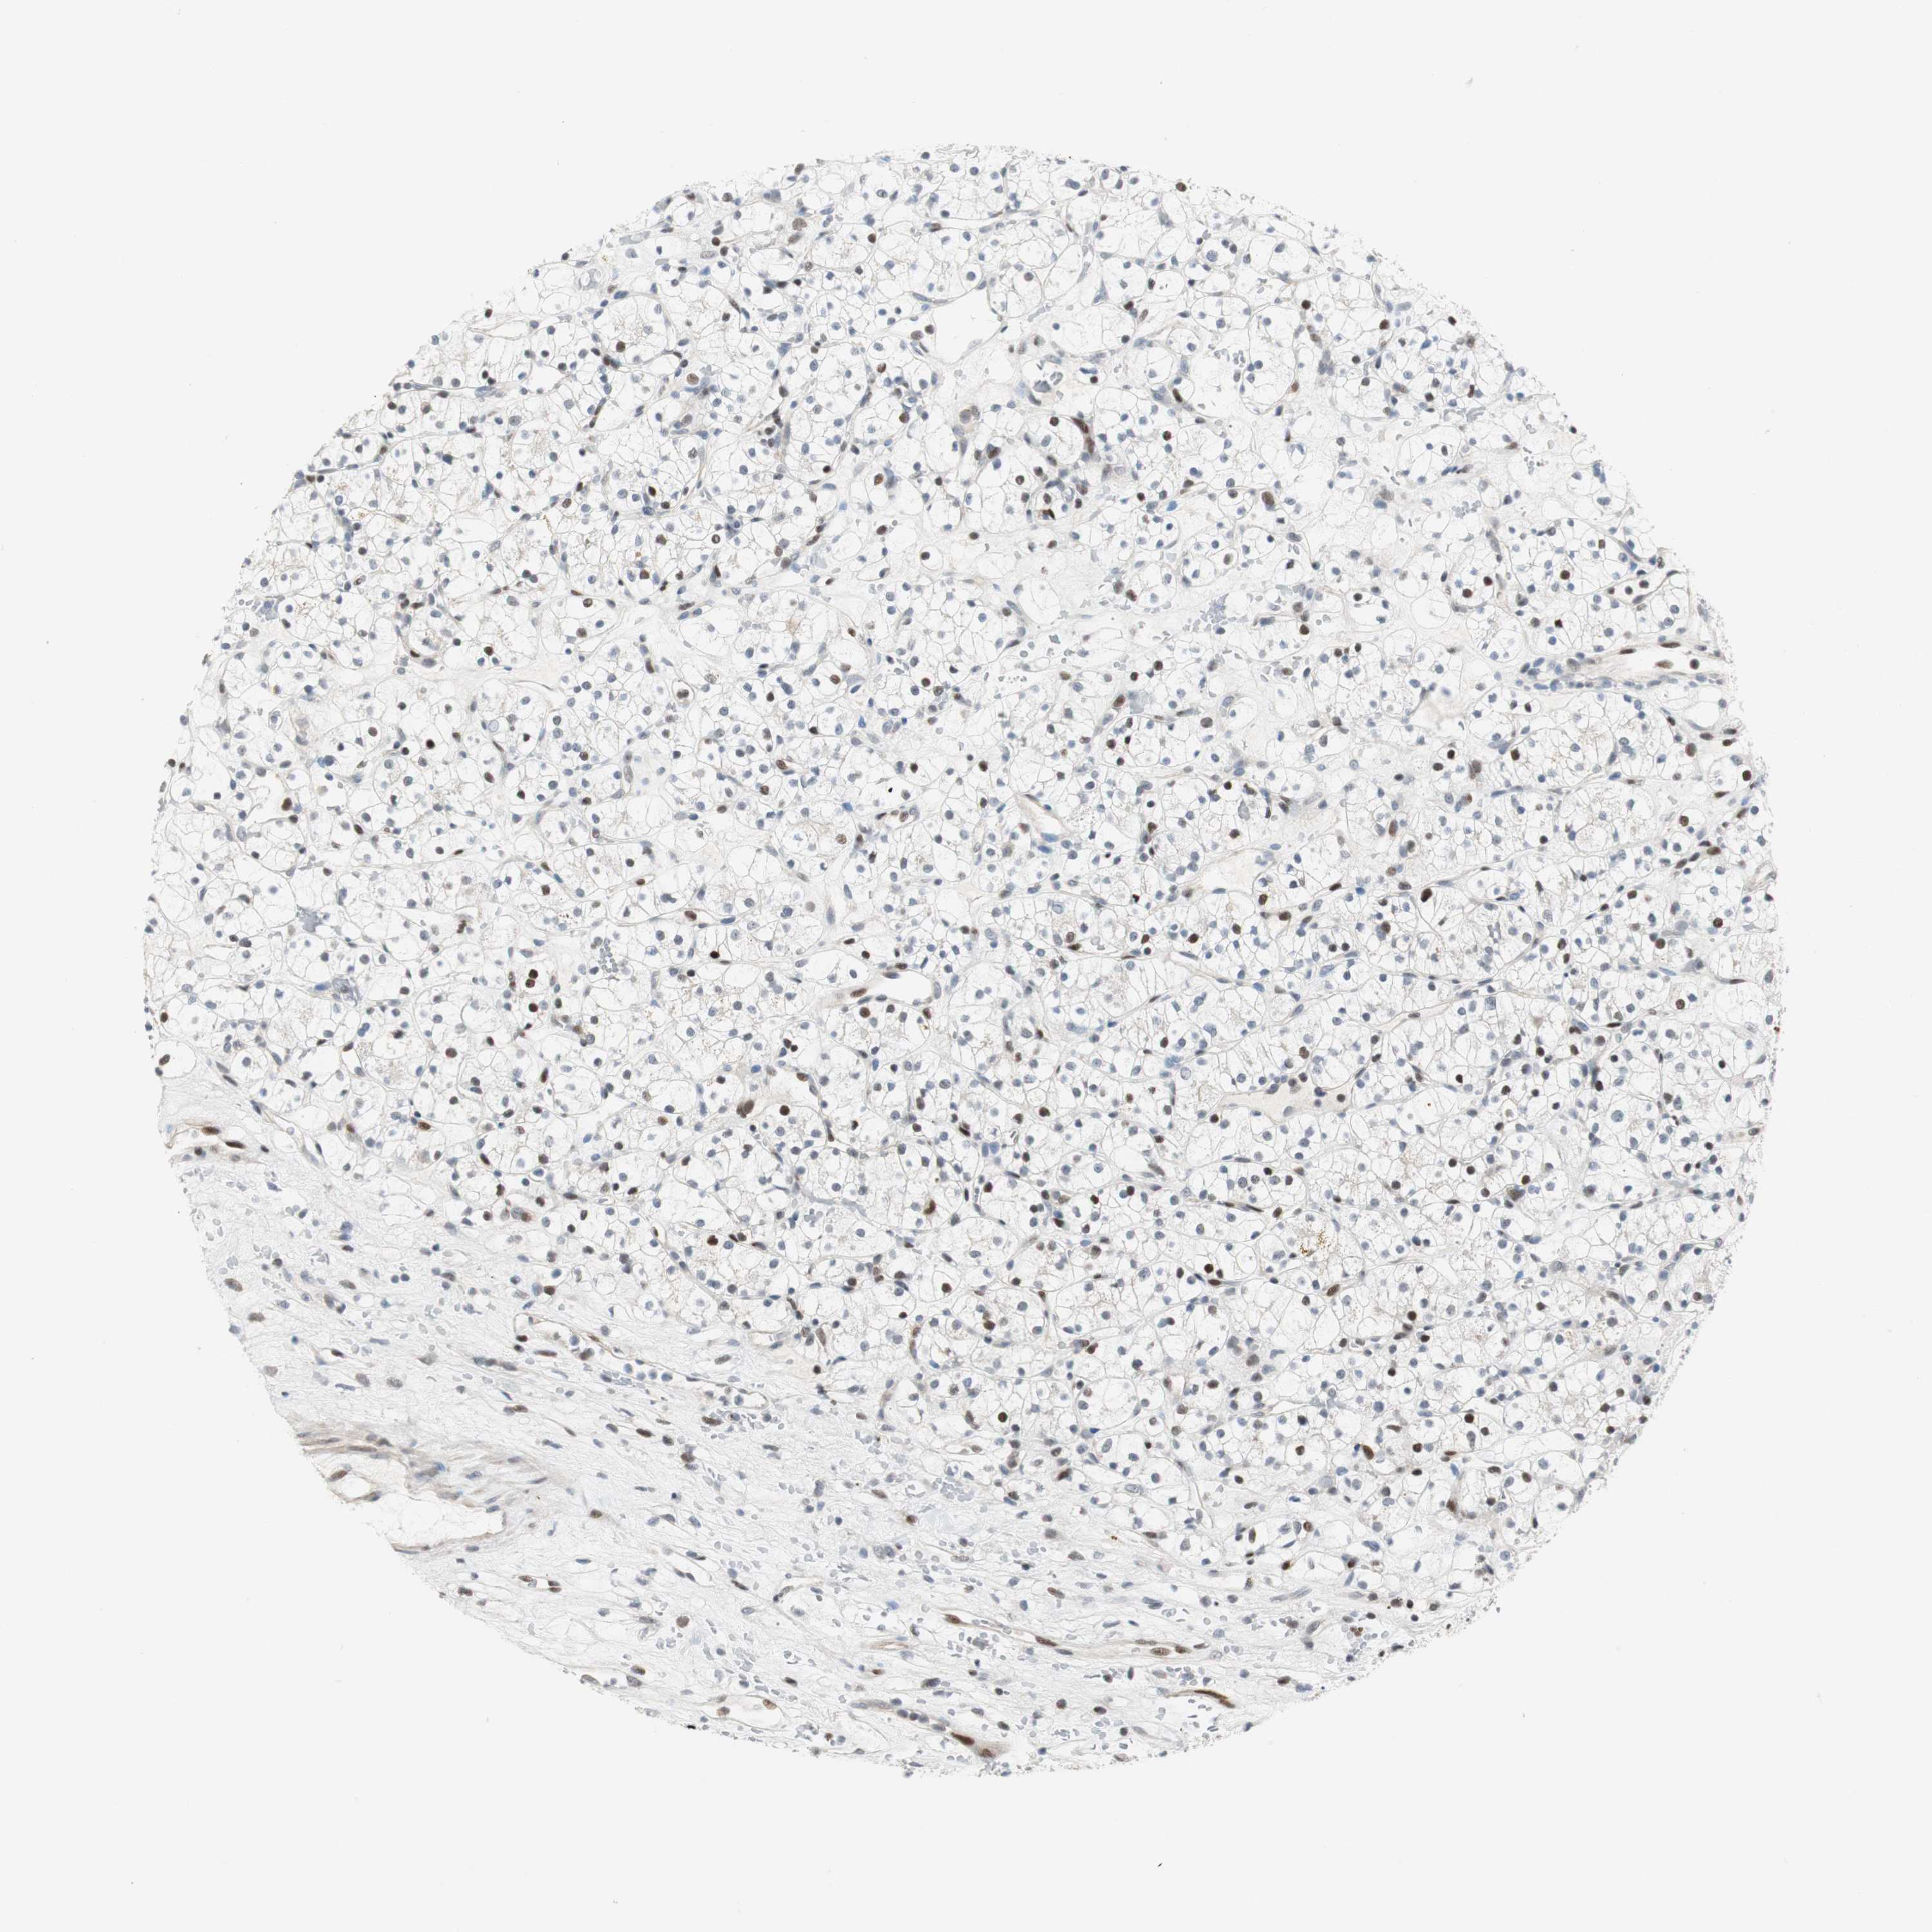

KIDNEY RENAL CLEAR CELL CARCINOMA (TCGA) - Interactive survival scatter ploti

The Survival Scatter plot shows the clinical status (i.e. dead or alive) for all individuals in the patient cohort, based on the same data that underlies the corresponding Kaplan-Meier plots. Patients that are alive at last time for follow-up are shown in blue and patients who have died during the study are shown in red.

The x-axis shows the expression levels (FPKM) of the investigated gene in the tumor tissue at the time of diagnosis. The y-axis shows the follow-up time after diagnosis (years). Both axes are complimented with kernel density curves demonstrating the data density over the axes. The top density plot shows the expression levels (FPKM) distribution among dead (red) and alive patients (blue). The right density plot shows the data density of the survived years of dead patients with high and low expression levels respectively, stratified using the cutoff indicated by the vertical dashed line through the Survival Scatter plot. This cutoff is automatically defined based on the FPKM cutoff that minimizes the p-score. The cutoff can be changed by dragging the vertical line or by entering a cutoff value in the square labeled "Current cut-off".

Under the Survival Scatter plot the p-score landscape (black curve; left axis) is shown together with dead median separation (red curve; right axis). Dead median separation is the difference in median mRNA expression between patients who have died with high and low expression, respectively. It is calculated as follows: median FPKM expression of dead patients with high expression - median FPKM expression of dead patients with low expression. This is intended to aid the user in visually exploring custom cutoffs and the associated p-scores and dead median separation.

Individual patient data is displayed and can be filtered by clicking on one or more of the category buttons on the top of the page. Categories describing expression level and patient information include: high, low, alive, dead, female, male and tumor stages. The scale of the x-axis can be toggled between linear and log-scale by clicking on the "x log" button. Mouse-over function shows TCGA ID, patient information and mRNA expression (FPKM) for each patient.

& Survival analysisi

Kaplan-Meier plots summarize results from analysis of correlation between mRNA expression level and patient survival. Patients were divided based on level of expression into one of the two groups "low" (under cut off) or "high" (over cut off). X-axis shows time for survival (years) and y-axis shows the probability of survival, where 1.0 corresponds to 100 percent.

RAD1 is potential prognostic, high expression is favorable in Kidney Renal Clear Cell Carcinoma (TCGA)

TCGA RNA samplesi

RNA-seq data is reported as average FPKM (number Fragments Per Kilobase of exon per Million reads), generated by the The Cancer Genome Atlas (TCGA) .

Normal distribution across the dataset is visualized with box plots, shown as median and 25th and 75th percentiles. Points are displayed as outliers if they are above or below 1.5 times the interquartile range. FPKM values of the individual samples are presented next to the box plot.

Average pTPM 5.7

Number of samples 521